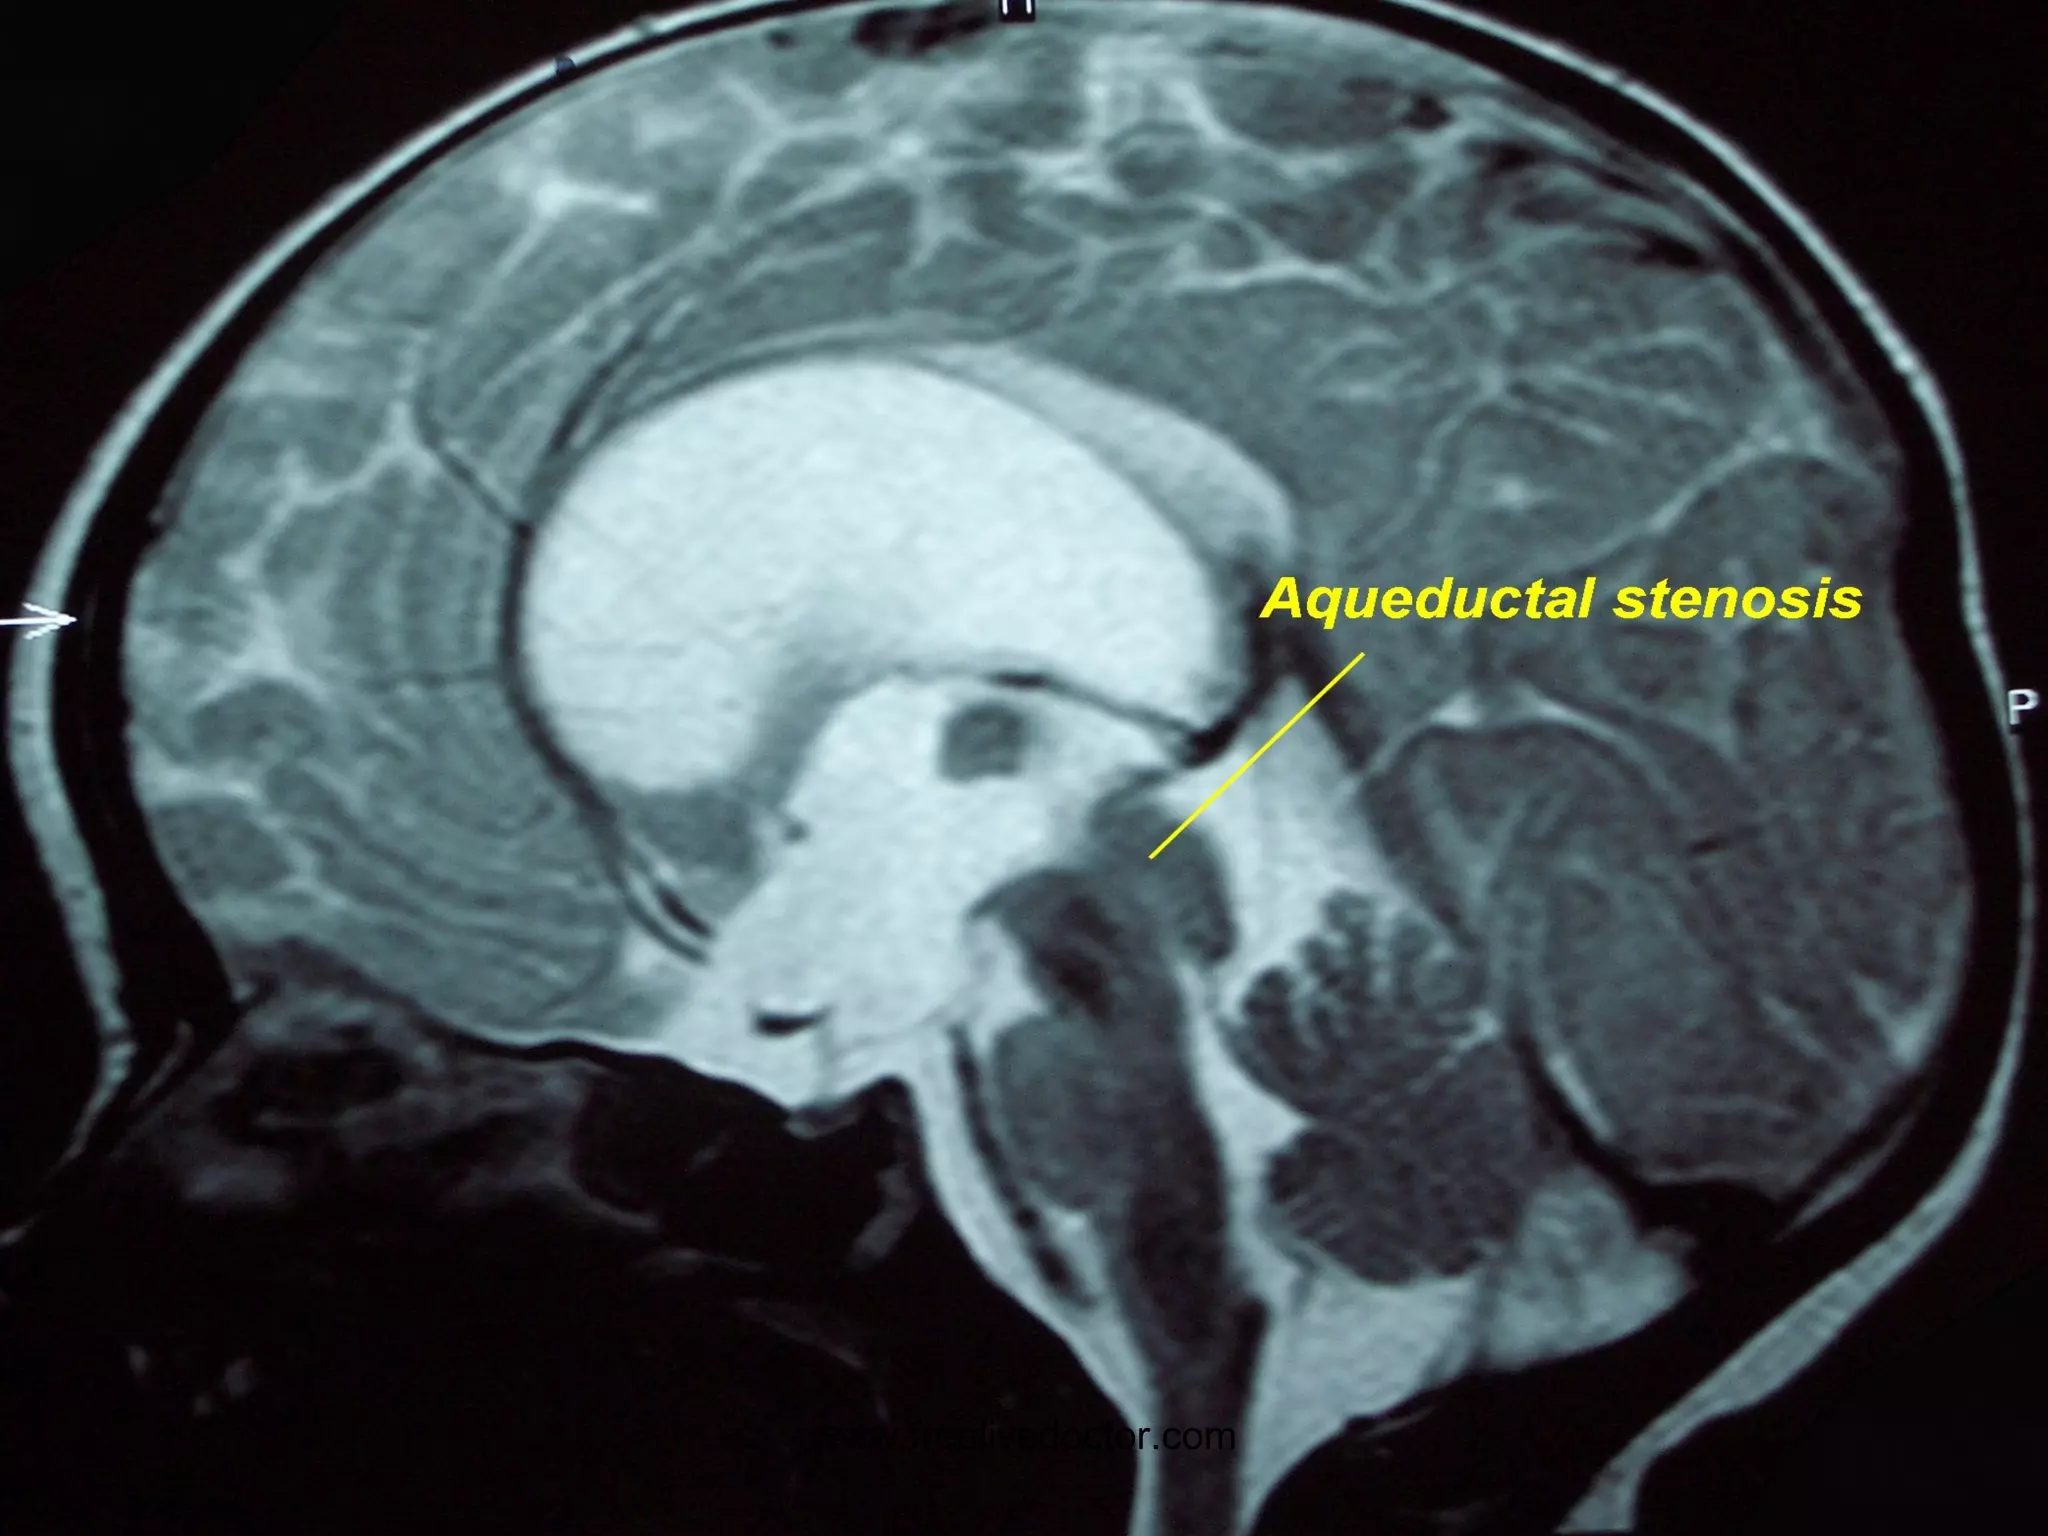

HYDROCEPHALUS www.freelivedoctor.com

HYDROCEPHALUS Impaired RESORPTION Increased PRODUCTION OBSTRUCTION COMMUNICATING (entire) NON-COMMUNICATING (part) HIGH Pressure NORMAL Pressure www.freelivedoctor.com

• #28 Basic pathophysiologic concepts about hydrocephalus which is defined as any major deviation from the normal physiology of CSF

• #30 Hydrocephalus on MRI

• #31 Hydrocephalus also showing cerebral edema, CT or MRI? Ans: CT Why? Ans: Bone is always very dense on CT, and water is always intense on T2 weighted MRI